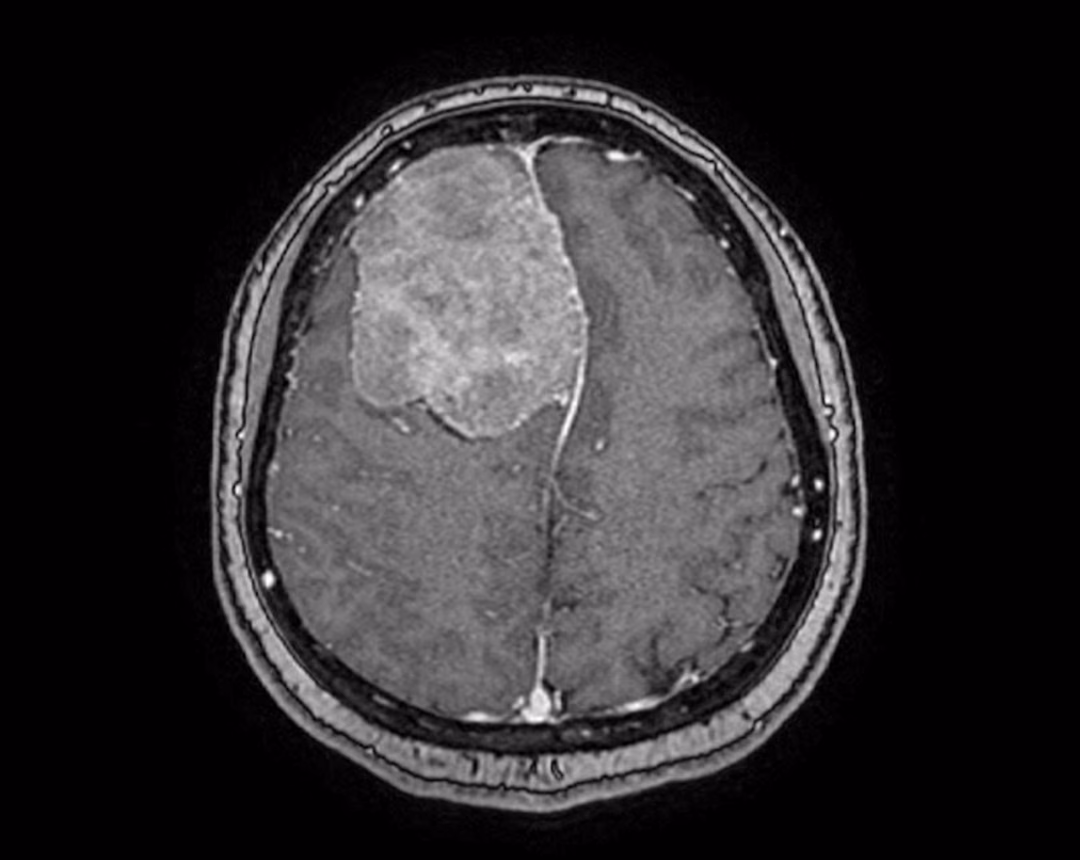

Chị Trịnh Nhật Khánh, một nữ võ sư 45 tuổi sống tại TP.HCM, là bệnh nhân mới nhất trải qua ca phẫu thuật này. Khối u màng não rất lớn, có kích thước lên đến 6cm, đã được phát hiện trong quá trình tầm soát đột quỵ tại Bệnh viện FV. Khối u này chèn ép gần 1/4 não, gây ra nhiều nguy cơ biến chứng nguy hiểm. Các bác sĩ đã nhận định rằng khối u cần được loại bỏ sớm để đảm bảo an toàn cho bệnh nhân.

Trước khi tiến hành phẫu thuật, các bác sĩ đã lên kế hoạch chi tiết, bao gồm việc thuyên tắc mạch máu nuôi khối u. Quá trình này giúp giảm thiểu rủi ro mất máu trong quá trình mổ, đảm bảo sự an toàn cho bệnh nhân. Hệ thống định vị dẫn đường thần kinh Navigation và hệ thống cắt đốt u bằng siêu âm đã được sử dụng để đảm bảo ca mổ thành công.

Ca phẫu thuật kéo dài 4 giờ đồng hồ, các bác sĩ đã bóc tách tỉ mỉ khối u và lấy ra khỏi não bệnh nhân mà không gây tổn thương mô não xung quanh. Đây là một thành công đáng kể, nhờ vào sự phối hợp chặt chẽ giữa các chuyên gia và công nghệ hiện đại. Chỉ 2 giờ sau mổ, bệnh nhân đã hồi phục ngoạn mục, đánh dấu một cột mốc quan trọng trong quá trình điều trị.